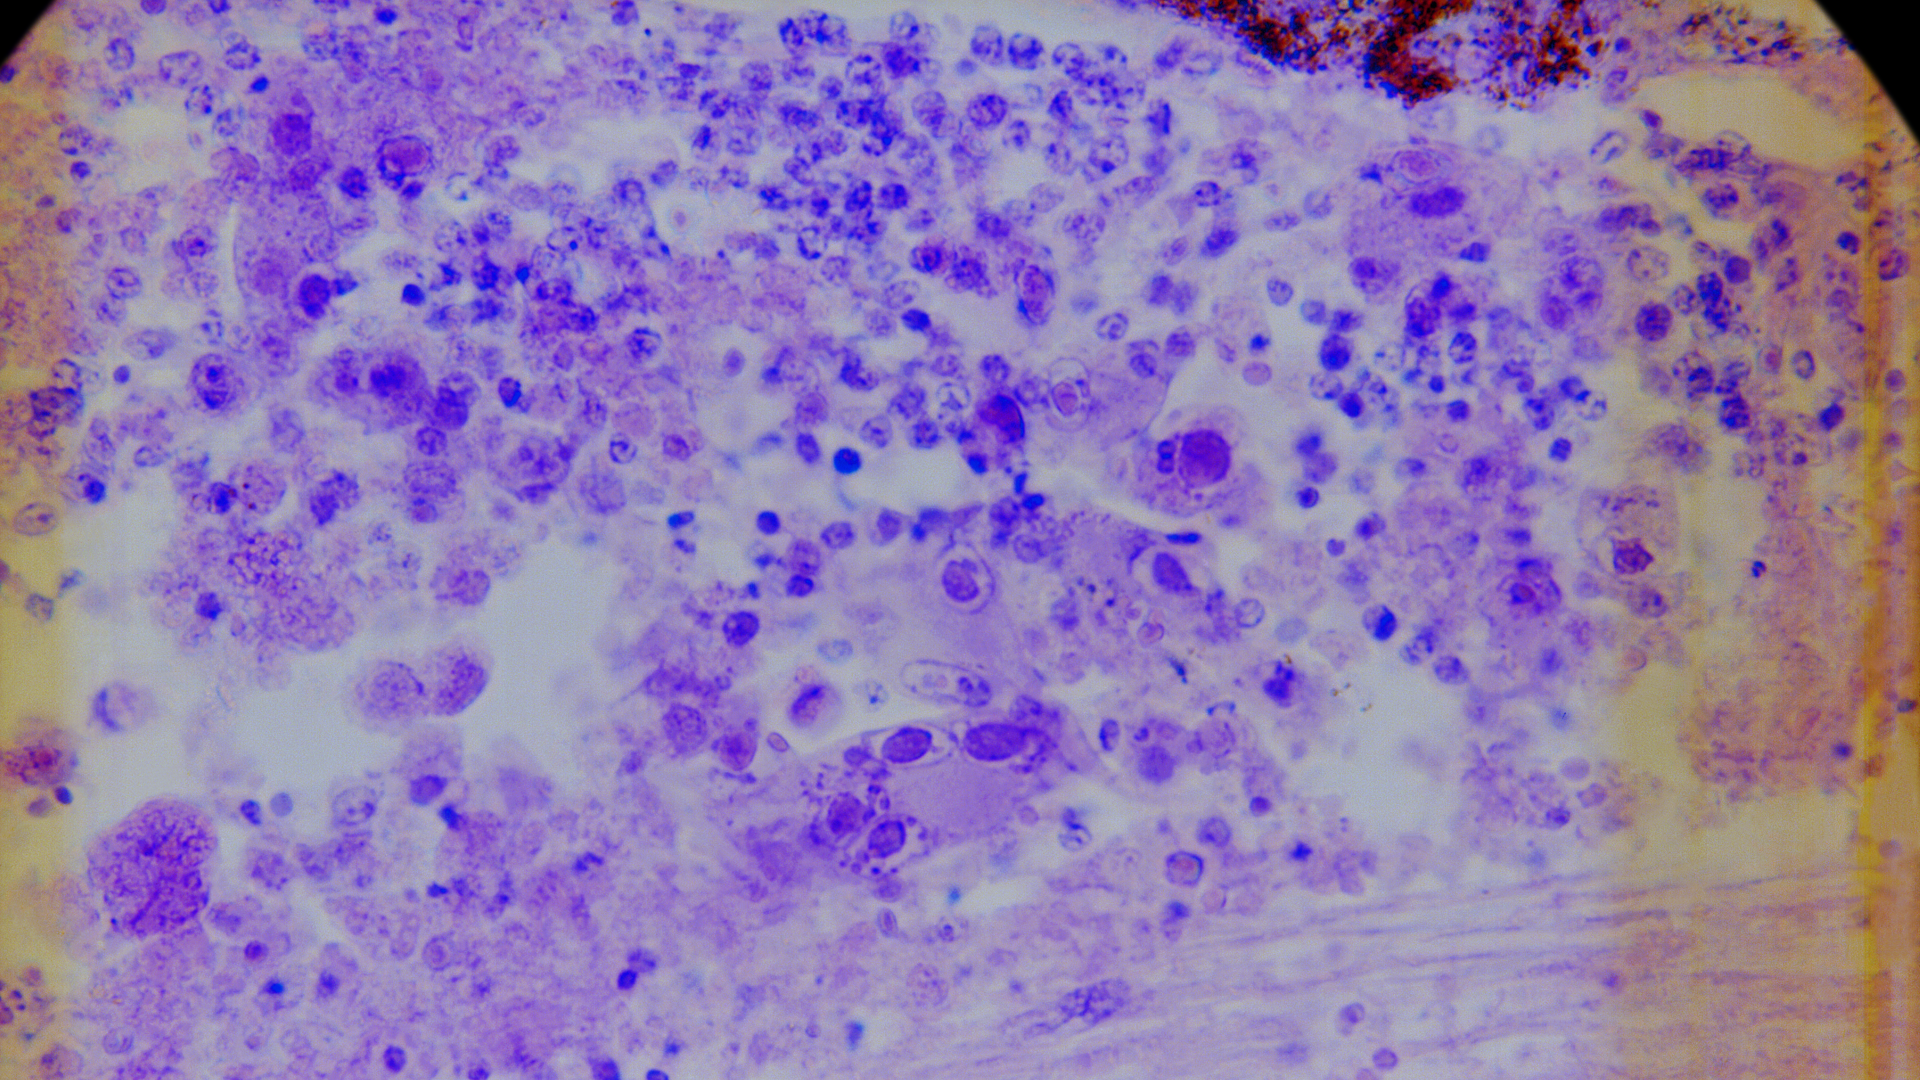

Axi-cel is an autologous anti-CD19 CAR T cell therapy manufactured from the patient’s own T cells, which have been extracted and then reprogrammed with CAR molecules to help the T cells recognize cancer cells. The reengineered T cells are infused back into the patient to attack the cancer.

High-risk LBCL is a subgroup of the disease in which patients have double- or triple-hit lymphoma or additional clinical risk factors identified by the International Prognostic Index (IPI) or interim positron emission tomography (PET) scan. Historically, less than half of these patients achieve long-term disease remission with typical treatment approaches like chemoimmunotherapy.